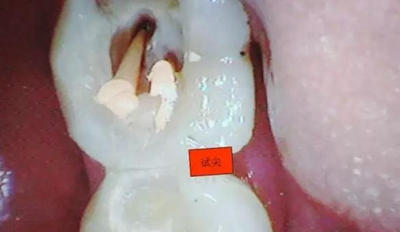

剛開始懷疑有增生的牙體組織,其實(shí)就是髓石。

3.開髓去腐后,髓腔基本就是這樣,在頰側(cè)近遠(yuǎn)中都有根管口顯示,初步用8號(hào)C+銼去試探性探查根管,沒有阻力感,以為就是c型根管,舌側(cè)用C+銼時(shí)有阻力感覺,接上測(cè)量?jī)x去探查根管,以防C+銼探通后超出根尖孔,最后舌根長(zhǎng)度16mm*15號(hào)K銼(16.5mm*8號(hào)C+銼),機(jī)擴(kuò)F2。接下來著重頰側(cè)的根管尋找,后來在頰側(cè)近遠(yuǎn)中插入K銼時(shí)總覺得K銼尖段都指向一個(gè)位置,感覺不對(duì),再次讀X線片,后來發(fā)現(xiàn)術(shù)前沒有仔細(xì)查看X線片,以及未回顧這位患者年齡,也就忘記牙齒的增齡性改變的含義。髓腔之所以小或者不清楚,一個(gè)因?yàn)槟挲g增加的原因二是因?yàn)檠例X長(zhǎng)期受到外界物理化學(xué)刺激所導(dǎo)致髓腔變小,甚至沒有髓腔顯影。本病例患者,髓腔有大概顯影,但髓室里好像有增生的牙體組織,其實(shí)就是髓石。并且和髓室底相連接。如果不注意,有可能按常規(guī)預(yù)備方法進(jìn)行預(yù)備。

4.接著與患者溝通后,同意繼續(xù)去除髓石,用細(xì)小的安全端金剛砂車針輕微的去除,沿著弧形方向切割,去除后發(fā)現(xiàn)不是2個(gè)根管口,而是一個(gè)根管口,有點(diǎn)類似下頜6遠(yuǎn)中根管口的樣子。(遠(yuǎn)中頰根16mm*15號(hào)K銼)